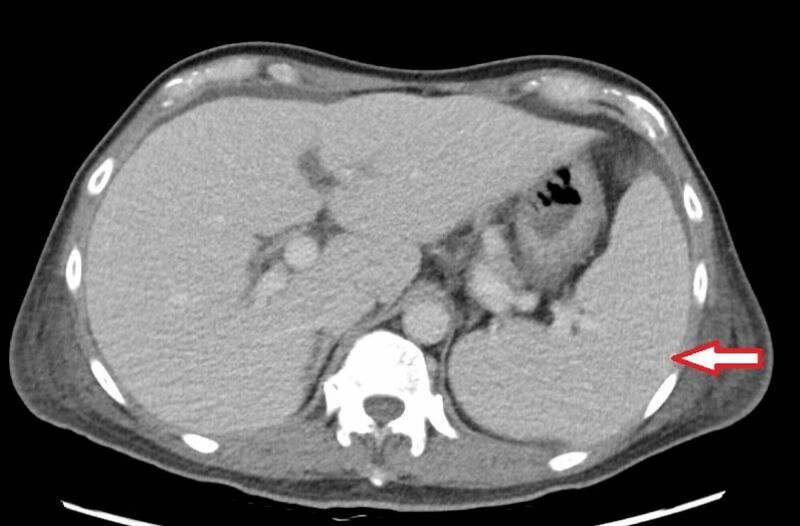

63歲林先生去年底開始出現不明原因反覆高燒,多次往返診所查不到原因,經到大醫院抽血檢查,顯示白血球、血小板及血紅素低下必須輸血,但血液及骨髓等檢查均找不到病因,僅電腦斷層意外發現他的脾臟腫大與腹水,最後在心臟超音波檢查中,發現罹患三尖瓣重度閉鎖不全,瓣膜上還長了1公分大的贅生物(細菌感染的病灶),確診為感染性心內膜炎,更換人工生物瓣膜,清除感染病灶後恢復健康。

楊凱文表示,若三尖瓣功能受損,血液逆流回右心房,使右心房壓力增加,進而影響全身血液回流,就會造成器官壓力上升,當逆流非常嚴重且延遲治療,少部分病人的肝脾會出現問題,例如肝硬化、脾臟腫大等,而脾臟是造血器官,若因此腫大,造成血球細胞破壞,就可能導致全身性血球減少,發生如林先生一般的情況。